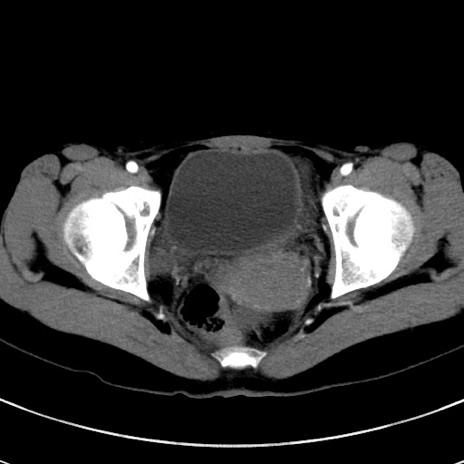

症例17(横断像)

【症例】20歳代女性

【主訴】嘔吐、下腹部痛

【現病歴】昨日夕食後に嘔吐し下腹部痛が出現。本日になっても嘔吐持続し改善しないため来院。

【身体所見】意識清明、BT 37.2℃、BP 108/67mmHg、腹部:平坦、やや硬、下腹部正中から右にかけて圧痛あり、反跳痛軽度あり、tapping pain(+)。

【データ】WBC 13600、CRP 14.94

冠状断像